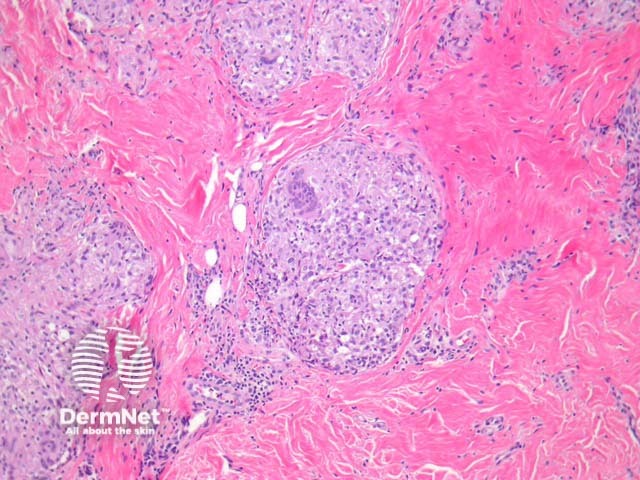

Tuberculoid leprosy – There is a tuberculoid or sarcoidal granulomatous reaction throughout the dermis consisting of some Langhans giant cells, macrophages in tight clusters, and few accompanying lymphocytes (figure 3). The infiltrate may extensively infiltrate peripheral nerves (figure 4, arrow), vessels, the overlying epidermis and arrectores pilorum.

Figure 3